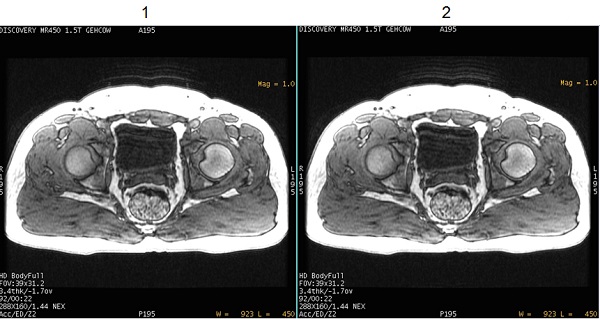

There are two NEX Mode options. Note that the scan time is the same for both options.

- Long term = 1, which acquires data first in an phase loop and then in an excitation loop. This data acquisition technique can reduce ghost-like artifacts induced from patient motion.

- Short term = 0, which acquires data first in an excitation loop and then in a phase loop. This is how data is acquired in previous software versions. Typically use this option if your site has an on-going clinical study with LAVA or LAVA-Flex images and you do not want to change any scan parameters or User CVs that would effect image appearance.

| 1 | Image acquired with NEX Mode User CV set to 1 or Long term. Note the reduced motion artifact. |

| 2 | Image acquired with NEX Mode User CV set to 0 or Short term. |